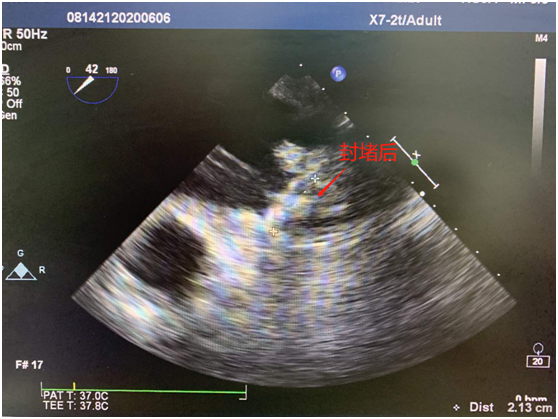

封堵后的左心耳